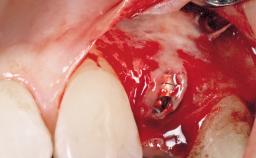

Immediate Placement of an Implant in a Maxillary Left Central Incisor Site

A 33-year-old female patient presented with an upper left central incisor that required extraction after a failed endodontic therapy. The tooth had been traumatized when the patient was a teenager and had undergone several endodontic treatments, including two apicectomy procedures. The patient was in good health and did not smoke. Clinical examination showed that the patient had a high lip line. In full smile, the gingival margins of the upper teeth were visible to the first molars. The gingival margins of central incisors 11 and 21 were only just showing. Examination of tooth 21 confirmed that the tooth was mobile and had hypererupted by 1 mm.

Placement Protocol Immediate implant placement

Socket Integrity Damage to one or more bone walls

Bone Volume Damage to one or more socket walls

Bone Augmentation Horizontal|Simultaneous

Augmentation Materials Xenogenous|Membrane